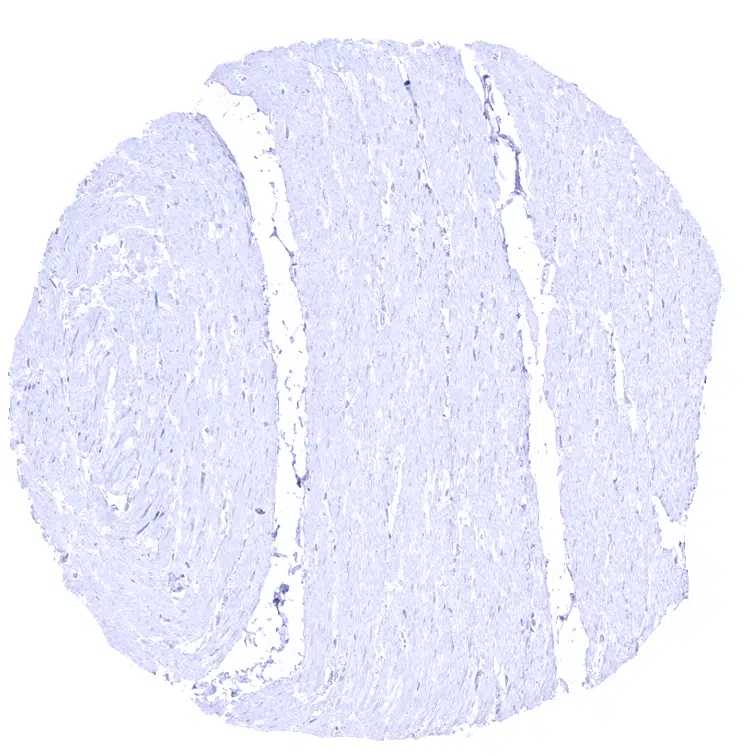

Uterus, myometrium